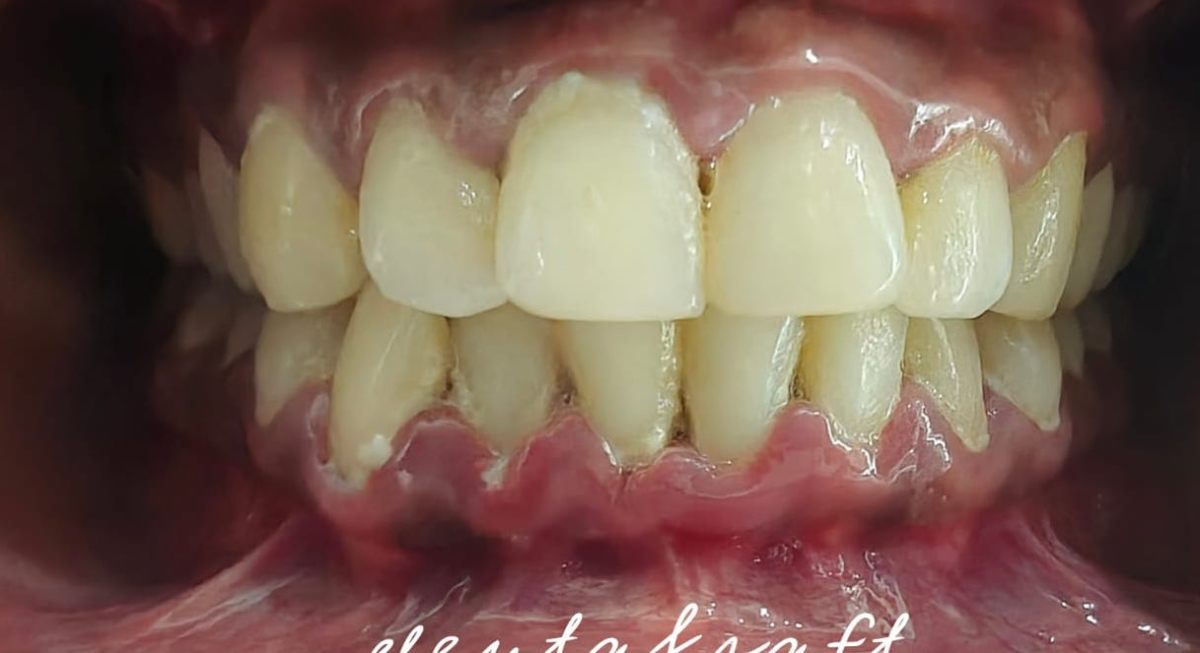

Our advanced laser gum treatment offers a minimally invasive and highly effective solution for improving gum health and treating gum disease. With the precision and selectivity of dental lasers, we can target and remove infected gum tissue while preserving the health of surrounding tissues.

Scaling and root planing, also known as deep cleaning, is a non-surgical procedure performed by our experienced dental professionals to treat and prevent gum disease. It is typically recommended when gum pockets are deeper than normal or when there is evidence of plaque and tartar buildup below the gumline.